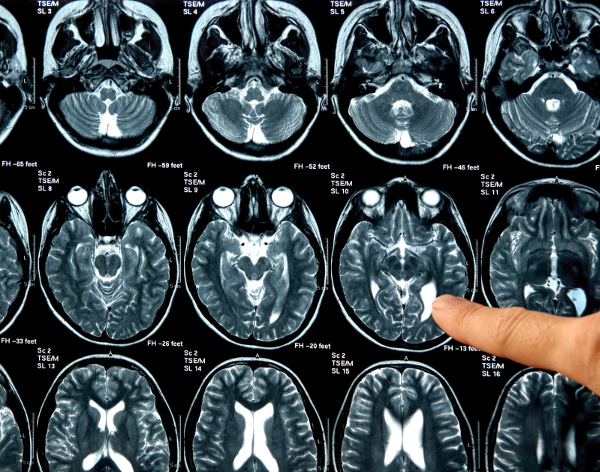

Tumore al cervello, “meccanismo di crescita scoperto è molto rilevante”

La crescita dei tumori cerebrali ha meno segreti. Dei ricercatori...